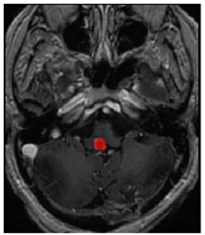

Table 3. Predictions with average dice scores.

Ground truthDeconvNetDeepMedic

Applsci 11 09180 i007 Applsci 11 09180 i008 Applsci 11 09180 i009

PSPNetU-NetV-Net

Applsci 11 09180 i010 Applsci 11 09180 i011 Applsci 11 09180 i012